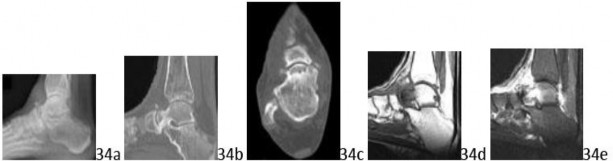

Q 1 1a 1b 1c 1d 1e A 43-year-old female factory worker has had a 6-month history of right plantar and lateral foot pain. She has pain with weight bearing and has difficulty standing at work. Management consisting of physical therapy, time off of work, and fracture boot immobilization has failed to provide relief. She is overweight and, as a result of the pain, cannot exercise to lose weight; thus she is getting worse instead of better. Examination reveals that the foot is not grossly swollen but is diffusely tender over the lateral, plantar, and medial hindfoot. The alignment is normal and the posterior calf muscles are mildly tight. A lateral radiograph is shown in Figure 1a and MRI scans are shown in Figures 1b through 1e. These findings are most consistent with which of the following?

DISCUSSION: The studies are most consistent with a stress fracture or insufficiency fracture of the anterior portion of the calcaneus. The radiograph shows normal findings. There is increased signal involving the inferior anterior aspect of the calcaneus on the T2-weighted images (Figures 1c through 1e), which is consistent with edema. There is also an abnormal trabecular pattern within this region with changes on the T1 and T2 images consistent with a stress or insufficiency fracture of the calcaneus. Whereas there is some increased signal from the os trigonum and the origin of the plantar fascia, these diagnoses are inconsistent with her symptoms. The MRI findings of osteomyelitis (decreased T1 signal and increased T2 signal) with secondary soft-tissue findings of adjacent soft-tissue ulcers, cellulitis, phlegmon, abscess, sinus tracts, or cortical bone destruction are not present. Complex regional pain syndrome has a wide spectrum of findings on MRI and is usually much more diffuse.

The Preferred Response to Question # 1 is 3.